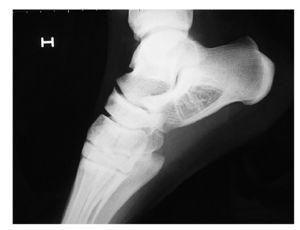

L'estudi radiològic es completa amb la realització de ressonància magnètica (RM) utilitzant plans sagitals, axials i coronals en T1, T2 i en short time inversion recovery (STIR) (fig. 2). La imatge STIR és molt útil en aquest cas, ja que suprimeix el senyal del teixit adipós normal.

Figura 2 Imatges de RM en tall axial T2 (A), tall axial STIR (B), tall coronal T1 (C) i coronal T2 fat sat (D). Lesió de senyal mixt en coll-cos de calcani de vores circumscrites de 33,4 x 3,5 x 2 cm. S'observen àrees de senyal adipós barrejades amb àrees de calcificació o ossificació d'aspecte trabecular en absència de senyal. S'observa també la presència d'una zona central d'aspecte quístic.